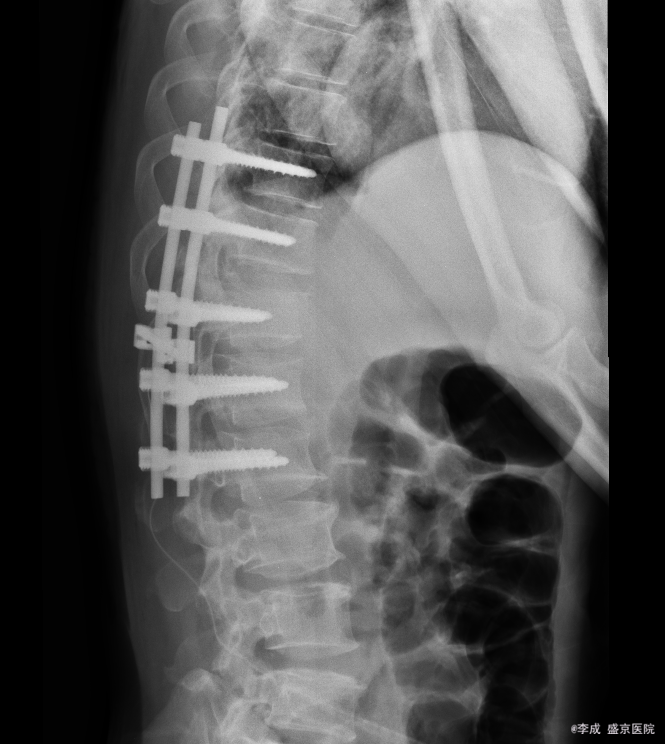

患者入院后完善相关检查,明确诊断,手术指征明确,于2015-11-17日于全麻下行胸椎后路椎板减压椎弓根钉棒系统内固定术,术后经抗炎、止疼等对症治疗后,患者恢复顺利,切口愈合良好,明日可出院。